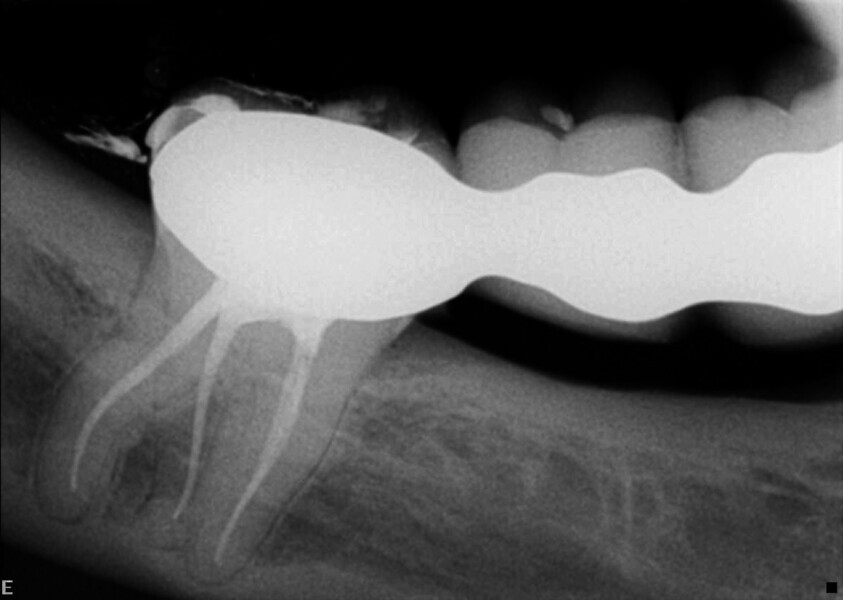

Le mode endodontique du nouveau logiciel DTX Studio Clinic permet d’ajouter de nombreuses vues et coupes transversales, ainsi que d’ajuster l’épaisseur des coupes pour vérifier le degré de calcification. Un autre avantage est la possibilité de tracer l’anatomie interne de chacune des racines et de l’ensemble du système, et de sélectionner une couleur pour chaque canal. Cette option est très utile pour examiner l’anatomie interne (Fig. 3).

Grâce à ce logiciel, il est donc possible de créer un modèle 3D de la dent et de visualiser le tracé des canaux et leurs longueurs de travail approximatives, ce qui nous donne une bonne idée de ce à quoi nous pouvons nous attendre (Fig. 4).

Dans le cas de cette deuxième molaire supérieure par exemple, la longueur de travail moyenne était d’environ 27 mm et quatre canaux étaient présents. Le type anatomique était ce que j’appelle un « double expresso », car il pose pas mal de difficultés. Ici notamment, la courbure du canal distal était très prononcée et prenait la forme d’un crochet au niveau de l’apex.

Toutes ces données sont précieuses pour choisir une séquence de limes nécessaire à la mise en forme et au nettoyage des canaux radiculaires. Le choix s’est porté sur les limes Traverse et ZenFlex de Kerr Dental (Fig. 5). Dans la racine distale, la lime 30/.04 n’a pas été utilisée dans les deux derniers millimètres, de façon à éviter toute déformation de cette zone. L’irrigation a été effectuée selon la technique dite « Séquence Sleiman » (article publié dans roots magazine 1/2014). L’obturation tridimensionnelle des canaux a été effectuée avec le système d’obturation éléments IC (Kerr Dental ; Fig. 6).